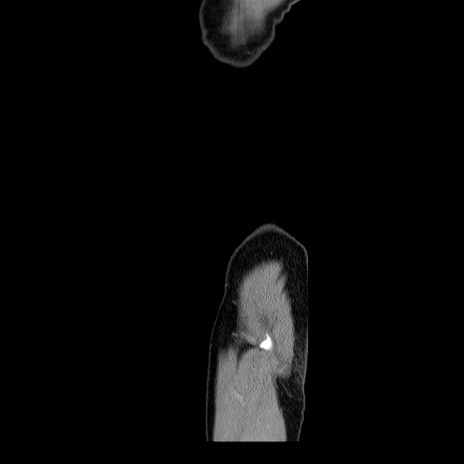

【症例】60歳代 男性

【主訴】右鼠径部膨隆

【現病歴】1年程前より右鼠径部膨隆あり。自己にて還納可能だったため放置していた。3時間前より右鼠径部の脱出を認め、還納困難となり受診。

【身体所見】右鼠径部に小児頭大の膨隆あり。弾性硬であり、用手還納は困難。左鼠径部にも膨隆を認める。脱出はなし。